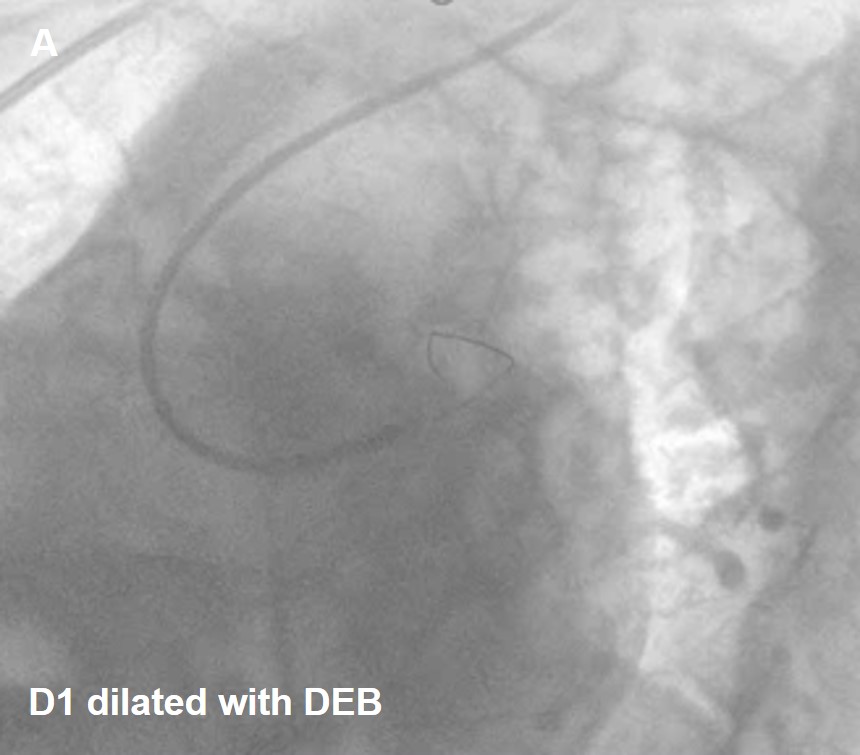

Procedure performedthrough right radial artery LMCA engaged with 6Fr EBU 3.5 Guiding catheter, 0.014X180cmRun-through wire placed in LAD and another Run-through wire was placed in Ramus.Predilatation done with 2.0x12mm Balloon. RAMUS stenting was done with 2.75X18mm Onyx DES. Diagonaldilatation done with 2.0 x 25mm PREVIL Drug Eluting Balloon. Thefinal result was good with TIMI III Flow without any edge dissection andresidual stenosis. Patient was discharged in a stable status on 3rd postprocedure day without any CV Symptoms.

Drug eluting balloons are helpful in places whereBifurcation and Trifurcation branching points are seen in a coronary vessel. Sothat we can avoid main vessels pinching. DEB can reduce metal load atBifurcation and Trifurcation anatomy.